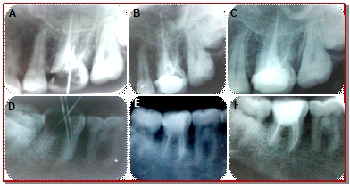

In the present study, the clinical outcome of mineral trioxide aggregate and Biodentine as repairing materials in the management of pulpal floor perforation was compared in vivo. Thirty teeth having pulpal floor perforation were enrolled in this study, out of which 15 perforations were repaired with mineral trioxide aggregate and the remaining 15 were subjected to Biodentine treatment. Following perforation repair, each tooth was then subjected to root canal therapy. Patients were recalled at 3, 6 and 12 month interval. The assessment of pain, pain on palpation, tenderness on percussion, and radiological evaluation was performed to determine the repair ability of pulpal floor perforation. Statistical analysis was performed with Chi-square test between the two groups and a value of p<0.05 was considered as statistically significant. The results showed that pain, tenderness on percussion as well as the thickness of periodontal ligament was gradually decreased and the communication between the perforation and oral cavity was successfully repaired following MTA and Biodentine therapy. Furthermore, the differences between MTA and Biodentine were not statistically significant. It can be concluded that clinical outcome and repair of pulpal floor perforation by Biodentine is almost similar to MTA.